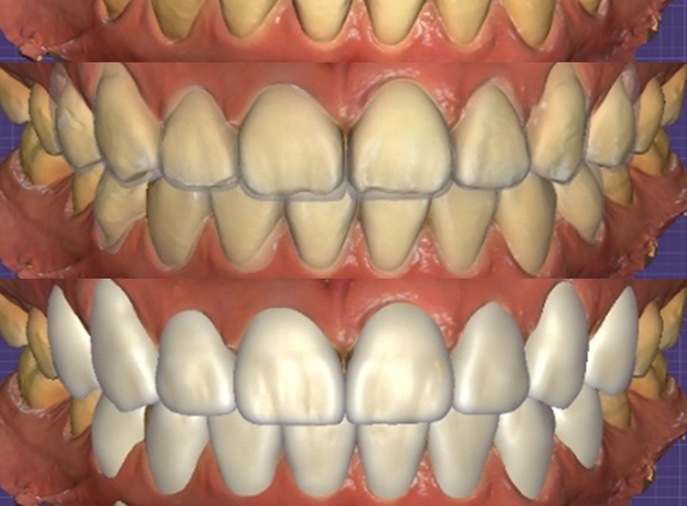

Design consultation (emphasizing natural beauty tailored for seniors)

The patient said,

“I don’t want them to be too white;

I’d like them to look like natural teeth.”

Accordingly, we based the design direction on

a translucency close to natural light,

a brightness that would not feel excessive,

a front tooth length that harmonized with the lip line,

and an incisal edge shape that would be comfortable for pronunciation.

After checking the expected result together

through the simulation screen,

the patient said, “That’s exactly the look,”

and decided to proceed with treatment.